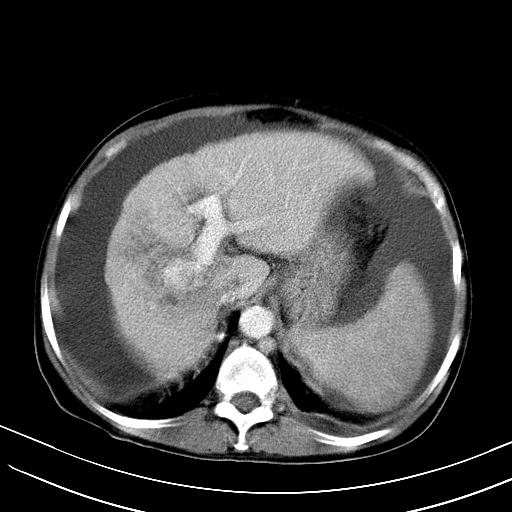

肝动静脉漏,动脉期肝动脉及门静脉内均可见造影剂……

1)肝右叶肝癌并肝动静脉漏。2)肝硬化,腹水。3)胆囊炎。

肝右叶肝癌并动静脉漏,肝硬化,腹水。

1)肝右叶肝癌并肝动静脉漏 门v右支瘤栓伴海绵样变。2)肝硬化,脾大 腹水。3)胆囊炎。门v高压.

右叶肝癌并肝动静脉漏(动脉期肝动脉及门静脉内均可见造影剂),肝硬化,腹水。(胆囊壁水肿)

1)肝右叶肝癌,考虑并发肝动静脉漏。扫描时间好像慢了。2)肝硬化,门脉高压、脾大、腹水。